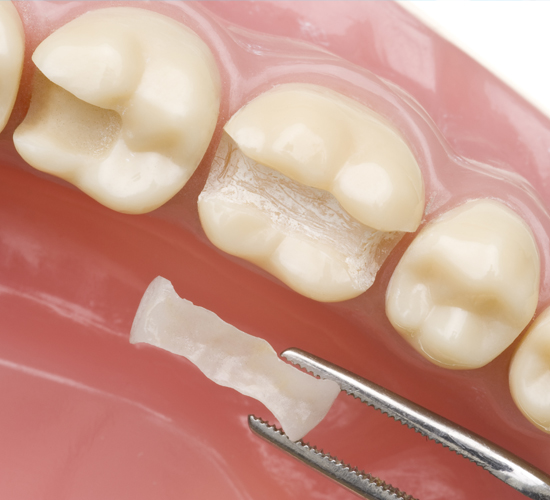

Hollywood Smile veneers are an excellent option for individuals looking to enhance the appearance of their smiles.

The versatility of veneers makes them a favorite for fixing minor imperfections in your teeth.